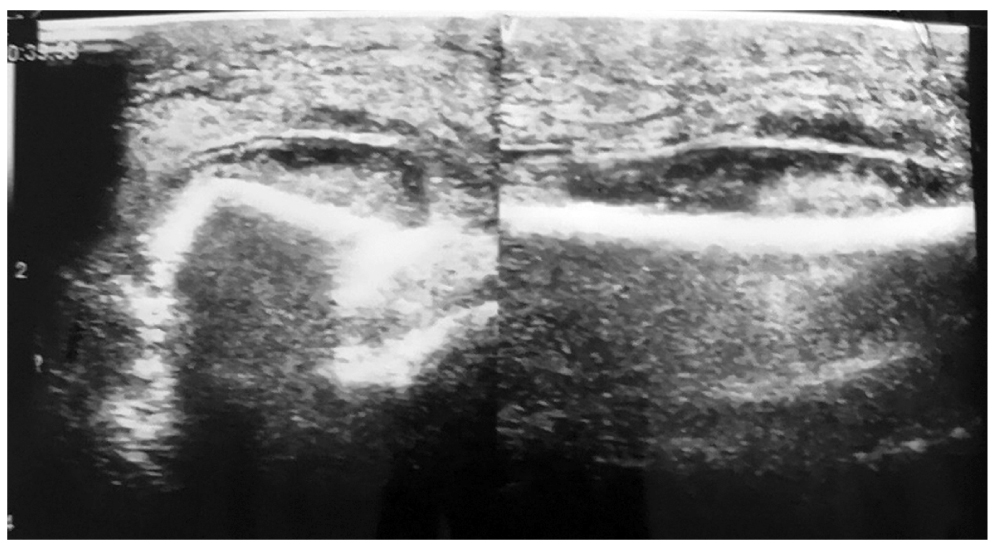

Рис. 1. Ультразвуковое исследование левой голени на 8 сут заболевания: под надкостницей в проекции нижней трети наружной поверхности малоберцовой кости определяется жидкость — участок высотой 40–42 мм, шириной 21 мм, толщиной до 6–7 мм с мелкодисперсной взвесью, баллотирует — параоссальная флегмона.

Fig. 1. Ultrasound of the left leg on day 8 of the disease: in the projection of the lower third of fibula external surface, liquid is seen — 40–42 mm high, 21 mm wide, up to 6–7 mm thick, with fine suspension, floating — paraossal phlegmon.

До операции УЗИ выполнено 8 (38%) пациентам. Реакция надкостницы, которая не была выявлена при стандартной РГ, выявлена у одной пациентки 12 лет на 8 сут заболевания (рис. 1). Параоссальная флегмона была интраоперационно вскрыта, при этом из костномозгового канала получен гной. При бактериологическом посеве выделен Staphylococcus aureus в титре 106 КОЕ/мл.